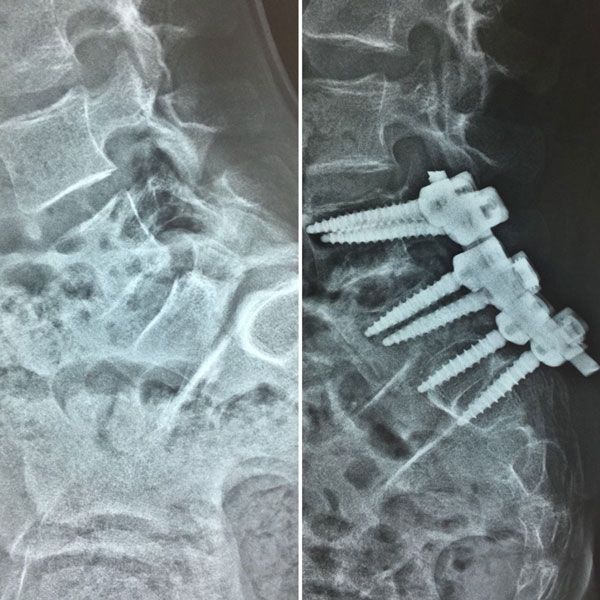

Спондилолистез - клинический пример